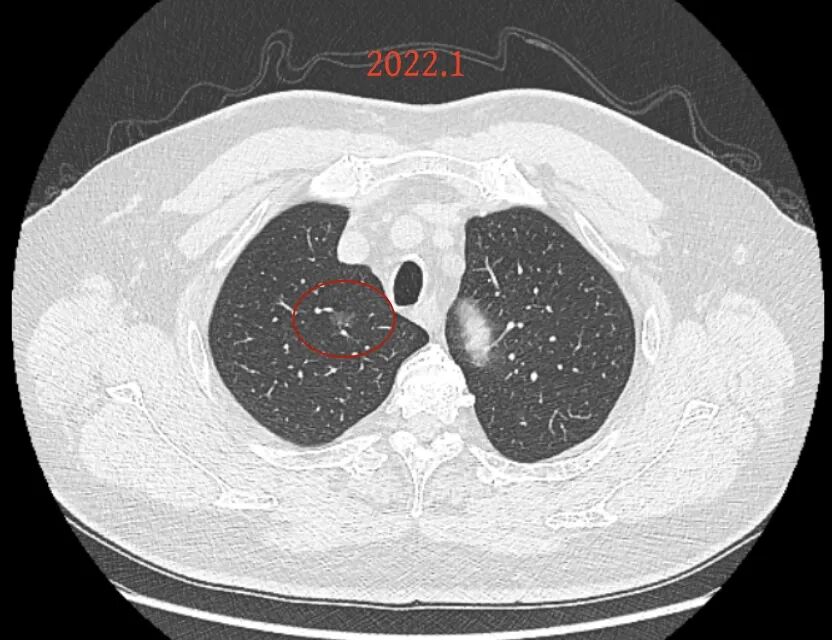

第一次问诊:2025.2

疾病描述:

肺磨玻璃结节随访观察了近4年,当地医生说有变化,动员我做手术切除,我想把这几年的C T电子胶片发给伍主任,请你诊断一下。是继续观察还是需要手术切除,右肺上页的两个结节能一次性切除吗?位置比较深能否保留尽量大的肺组织。

我的意见:

方形的是25年的,红色的主病灶,磨玻璃密度伴少许略偏高点密度,但还说不上典型混合磨玻璃病灶,考虑原位癌或微浸润性腺癌可能性大;蓝色的轮廓与边界欠清,位置靠上叶中央,无法段切或楔切;黄色的多发均淡而纯,分布在两肺。圆形粉色的是主要的两处23年时的样子,对比说不上很明显进展。鉴于若手术得切肺叶,何况两肺他处仍的结节,年纪又74了。我倾向保守点,先6-9个月复查,等进展并风险增加再来考虑怎么办的事。意见供参考!

我的想法是主病灶在右上叶,且多发,而且位置较深,若手术很可能要切且叶,虽考虑是肿瘤范畴的,但由于不管病灶A还是病灶B均仍是磨玻璃密度,没有纵隔窗可见的实性成分,在两肺多发病灶的情况下,适当保守点再随访下,待有进展并风险增高再干预也不至于影响预后。而且根据既往经验,磨玻璃密度的肺癌基本太会短时间内快速进展。

先回顾此前的影像及细节:

病灶没有确切纵隔窗可见的实性成分,但与血管关系较为密切。